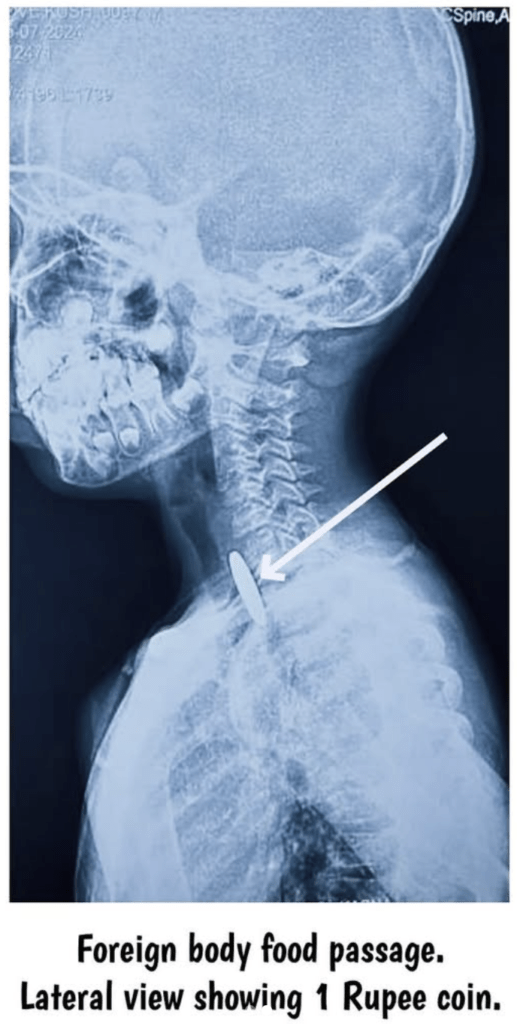

- Radiographic Imaging: Posteroanterior and lateral X-rays of the neck, chest, and abdomen help identify radio-opaque objects and their locations. Radiolucent objects may appear as air bubbles in the cervical oesophagus. Identification of the location of a swallowed or inhaled coin on X-ray depends on how it appears in AP and lateral views. In the trachea, the appearance is the opposite: it looks like a line on AP view and round on lateral view. In the oesophagus, the coin usually looks round on AP view and is seen end-on or as a line on lateral view. This difference is because the oesophagus is wider from side to side than front to back, whereas the trachea is wider from front to back than side to side. Disc/Button Battery exhibits a “Double Ring” or “Halo Sign” on the PA view, which is due to the central electrode separator and outer casing. This is a critical sign for early identification!

- Coin X-ray Sign: Round on PA view – Oesophagus (Lies in coronal plane).

- How can I differentiate a coin in the trachea from a coin in the oesophagus on an X-ray? A coin in the oesophagus appears round on the PA view because it lies in the wider coronal plane; a coin in the trachea appears line-like on the PA view because it lies in the wider sagittal plane.